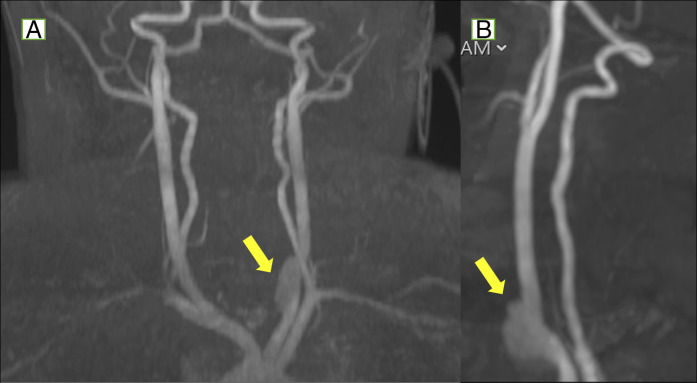

纽扣电池误食是小儿异物急诊的重要原因,往往会导致严重的并发症。我们提出的情况下,一个婴儿谁发展左总颈动脉食管瘘后纽扣电池摄入,这是进一步复杂的假性动脉瘤的形成。通过随访影像确诊,假性动脉瘤成功使用分流支架治疗。患者保持临床稳定,无神经功能障碍。这一病例强调了早期诊断和干预对预防出血和中风等危及生命的并发症至关重要。此外,它强调了随访影像学研究的必要性,即使在无症状的患者中,也可以监测延迟并发症并告知正在进行的治疗。

Button battery ingestion is a significant cause of pediatric foreign body emergencies, often leading to severe complications. We present the case of an infant who developed a left common carotid-esophageal fistula after button battery ingestion, which was further complicated by the formation of a pseudoaneurysm. The diagnosis was confirmed through follow-up imaging, and the pseudoaneurysm was successfully treated using a flow diversion stent. The patient remained clinically stable without neurological deficits. This case underscores the critical importance of early diagnosis and intervention to prevent life-threatening complications such as hemorrhage and stroke. In addition, it highlights the necessity of follow-up imaging studies, even in asymptomatic patients, to monitor for delayed complications and inform ongoing management.